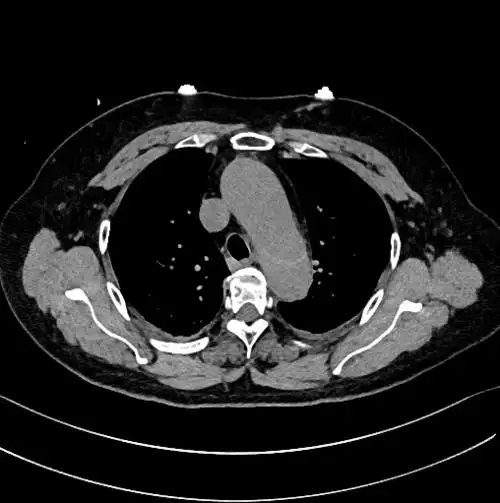

主动脉夹层详细图解 - 好大夫在线

又又双双叒叕主动脉夹层了

经典图谱ct平扫诊断主动脉夹层

简称主动脉夹层.

斯坦福a型主动脉夹层

胸背疼痛务必及时就医警惕凶险的主动脉夹层